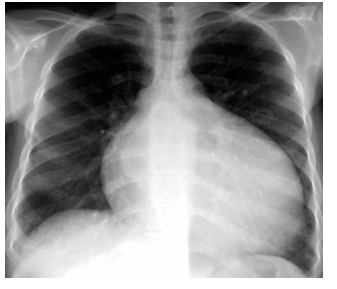

Leia o enunciado a seguir e responda a questão.

Paciente do sexo feminino, 66 anos, com antecedentes de tabagismo, hipertensão arterial sistêmica e diabetes mellitus tipo 2, procura atendimento médico com queixa de desconforto retroesternal tipo queimação e opressão que se iniciou há 1 mês, desencadeado aos grandes esforços. Há 1 semana passou a apresentar os mesmos sintomas em repouso, associados à dispneia, com duração de até 8 minutos e melhora espontânea. A paciente faz uso de valsartana 80 mg, glimepirida 4 mg e metformina 1000 mg. O exame físico é normal, PA = 150x85 mmHg e frequência cardíaca de 96 bpm. O eletrocardiograma está ilustrado a seguir.